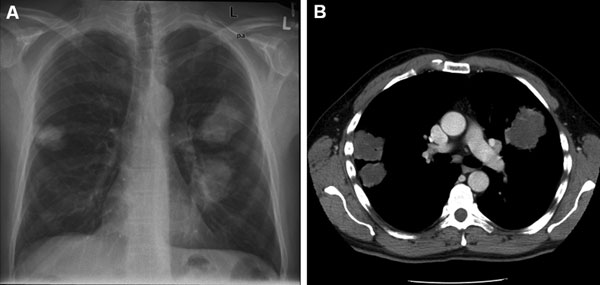

感染した人のレントゲン写真